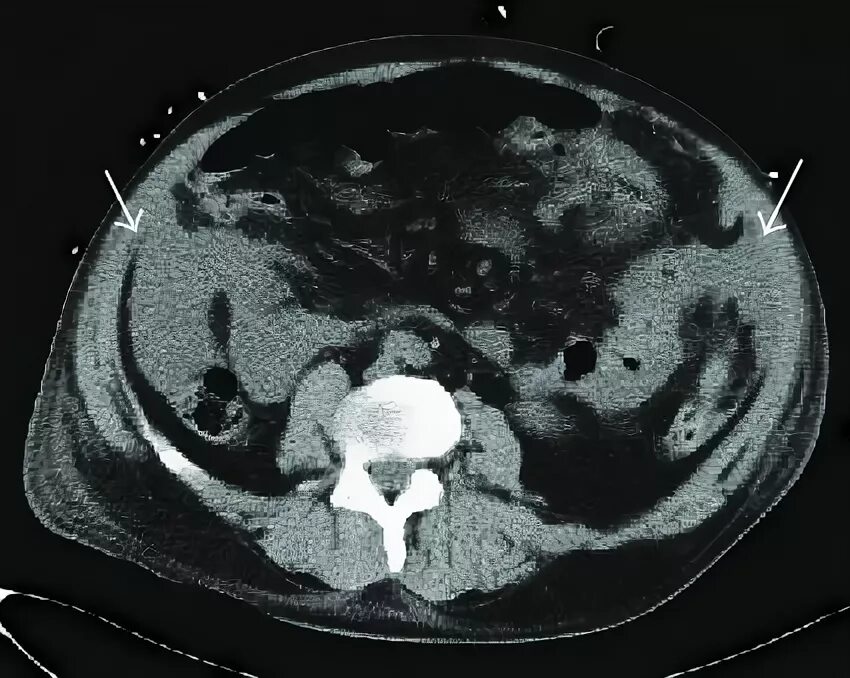

Побочный эффект кт